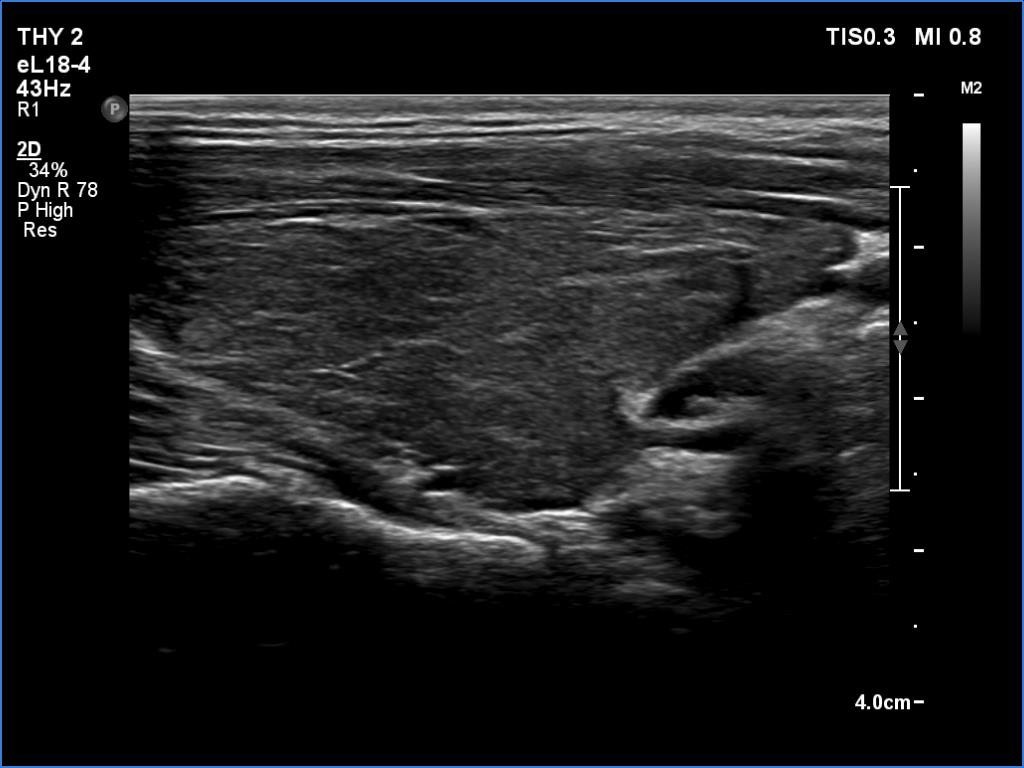

Ultrasonography. The thyroid was moderately hypoechoic and inhomogeneous. There was a deeply hypoechoic lesion in the isthmus which presented microcalcifications. Compared with the extranodular tissue, the nodule was much less vascularized on Doppler and microflow imaging but was harder on elastography.

There were two conditions which favored that the discrete lesion in the isthmus is a true nodule and not a more active focus of the underlying Hashimoto's thyroiditis. Firstly, the palpation which itself was suspicious of a cancer. Second, the presence of microcalcifications. It is worth comparing the similarly deep hypoechoic areas in the left lobe with the presentation of the cancer focus.